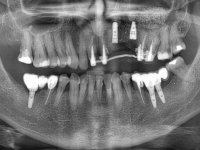

66-year-old male patient, non-smoker. It featured a 5-member metal-ceramic bridge with extreme mobility. Teeth 11 and 21 had infiltrated cervical margins. Both arches showed root exposure with signs of cervical abrasion. Composite resin “slots” were visible on the buccal surfaces of some mandibular teeth compatible with an orthodontic treatment with aligners that the patient was undergoing. After the imaging examination, it was found that the bridge's distal support, tooth 24, was irretrievably lost. The mesial pillars 11 and 21 had endodontic treatment and intraradicular posts. Teeth 25 and 26 also had endodontic treatment and extensive restorations in composite resin. In the lower jaw, two bridges were visible. In the third quadrant a 4-element bridge supported on tooth 35 and on 2 implants placed in the location of teeth 36 and 37. In the fourth quadrant a 3-element bridge supported on tooth 45 and an implant placed in the location of tooth 46. The patient presented a thick gingival phenotype and very good oral hygiene.

The patient was proposed to undergo a fixed oral rehabilitation consisting of a 2-element bridge over teeth 11 and 21 and a 5-element bridge over 3 implants that would be placed in the location of teeth 22, 24 and 26. The prosthetic structures would have an infrastructure in Zr coated with ceramic and the bridge over the implants would be screwed. The indicated extraction of teeth 25 and 26 and placement of an implant in the 26 site would imply surgery to fill the maxillary sinus. As the patient showed interest in having fixed temporary rehabilitation during treatment, we divided the treatment into 6 phases to achieve this goal: 1- Placement of a temporary bridge over teeth 11,21,25 and 26. With tooth extraction 24. 2- Placement of 2 implants in the location of teeth 22 and 24. 3- Placement of a temporary 6-element bridge over teeth 11 and 21 and over the implants. 4- Carrying out surgery to fill the maxillary sinus. 5 – Placement of the implant in the location of tooth 26 and in the area where the filling of the maxillary sinus was made. 6 – Placement of the definitive work.

A temporary acrylic bridge made in the laboratory with 7 elements was made, with teeth 11,21, 25 and 26 as pillars. The old bridge was removed and tooth 24 was extracted. The provisional bridge after relining was cemented in the mouth. Two implants were placed in the teeth 22 and 24 and 3 months after this intervention an impression was made to make a temporary bridge screwed over the implants and cemented to the teeth. The bridge was placed in the mouth and teeth 25 and 26 were extracted. 3 months later, surgery was performed to fill the maxillary sinus and 6 months later the implant was placed in the location of tooth 26. After osseointegration of this implant, the final impression was made for the final work. The bridge over the implants was permanently screwed on and the bridge over the teeth was cemented with resin-reinforced glass ionomer cement.